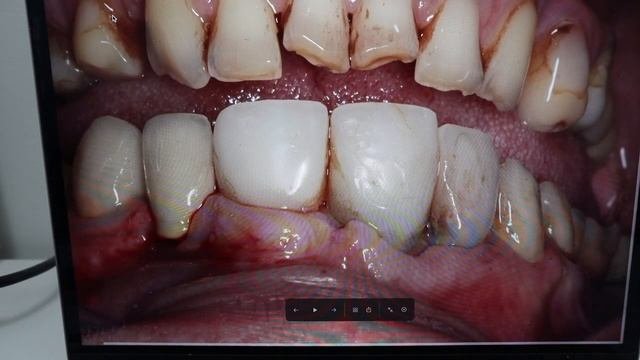

СТОМБУДНИ#18 ЧТО КУПИЛ НА ВЫСТАВКЕ_ #стоматология

Стомбудни#8.  ОТКУДА ДОСТАЛ ЗУБ_  ПЕРЕДЕЛЫВАЮ СВОЮ РАБОТУ

Стомбудни #6.  НИКОГДА ТАК НЕ ПРОТЕЗИРУЙ

СТОМБУДНИ#17  МАТЕРИАЛЫ! ЧЕМ РАБОТАЮ_ #стоматологическиематериалы